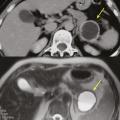

Toujours parmi les LKP rares à potentiel malin, on compte les tumeurs neuro-endocrines (TNE) kystiques (20 % des TNE pancréatiques) [fig. 5]. De découverte fortuite et non fonctionnelles, les TNE kystiques sont uniques, uniloculaires, bien différenciées, de bas grade, c’est-à-dire avec un indicateur de prolifération Ki67 < 3 %, et la présence d’une masse hypervasculaire (nodule) au niveau de la paroi. La partie charnue tissulaire peut être de petite taille.

La prise en charge a longtemps reposé sur une résection systématique des lésions, indépendamment de leur taille ou de leur grade. Des essais prospectifs européens sont en cours pour évaluer le risque de métastases ganglionnaires et à distance en cas de surveillance, pour ainsi valider (ou non) une attitude attentiste.

Selon l’âge et les comorbidités, on peut recommander de surveiller les TNE mesurant moins de 2 cm avec une imagerie en coupe (scanographie ou IRM) tous les six mois pendant dix-huit mois puis tous les ans. En cas de résection, une chirurgie d’épargne est à proposer pour les tumeurs mesurant moins de 2 cm.